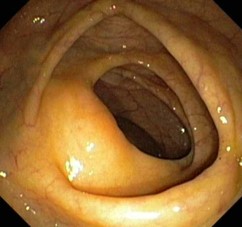

Kapselendoskopie des Dünndarms

Die Kapselendoskopie ist ein Verfahren zur Untersuchung des Dünndarms.

Hierbei wird eine erdnussgroße Kapsel geschluckt, die eine Digitalkamera, deren Stromversorgung sowie einen Sender beinhaltet. Die Videokapsel sendet über 8-10 Stunden pro Sekunde mehrere Bilder aus dem Magen- Darm-Trakt an einen Datenrecorder, den der Patient am Körper trägt.

Die aufgezeichneten Bilder werden rechnergestützt zu einem „Video“ verarbeitet, was dem Untersucher die Auswertung ermöglicht.